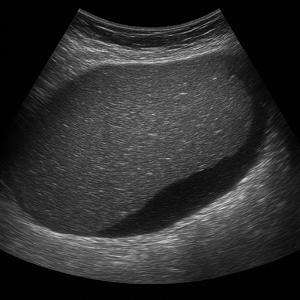

복부 종양과 복수

- 복부 종양(낭종, 종양)

간, 신장, 또는 다른 복부 장기에 생긴 혹들은 초음파에서 덩어리로 보여요. 가끔은 원래 장기가 아닌 곳에 생긴 종양도 보여요. - 복수 (복강 내 물)

배에 물이 고이는 현상이에요. 초음파로 액체가 있는 곳을 쉽게 볼 수 있어서, 복수가 있는지 확인할 때 매우 유용해요.